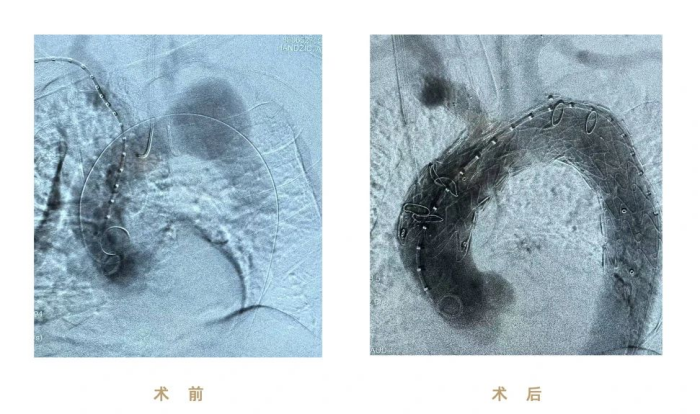

本例手术患者罹患复杂主动脉弓动脉瘤,累及左锁骨下动脉及降主动脉,并伴明显血管弯曲与结构异常,术中面临多项高难度挑战:

① 弯曲解剖结构导致支架定位偏差风险高,极易影响分支对位与瘤体隔绝效果

② 左锁骨下动脉因受瘤体挤压呈弯折状态,分支支架植入时导丝通过、支架输送困难

③ 主动脉弓毗邻心脏、气管等重要器官,操作空间狭窄,术中容错率极低

(图:术前、术后影像)

本次手术使用彩神在线网信彩票-彩神通免费版下载-彩神8争霸vlll-彩神购彩购彩大厅-彩神软件陆立根免费版-彩神ll争霸3-彩神ll彩神8-彩神ll争霸彩票-拼搏在线彩神网网页版CS一体式弓部三分支重建系统进行腔内修复,逐次完成通路建立、CS主体支架植入及精准释放、弓上三分支(无名动脉、左颈总动脉、左锁骨下动脉)依次超选及分支支架植入,全程造影显示支架形态良好、无移位及内漏、三分支血流通畅,达到理想的隔绝与血供重建效果。